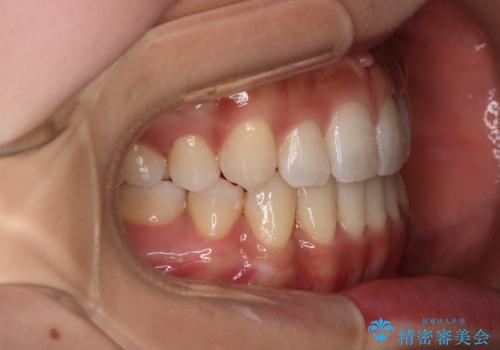

【審美装置】八重歯気になる

- 八重歯と叢生を主訴に来院されました。なるべく健康な歯を残したいという患者様の希望から、右側上下4番抜歯をしてワイヤー矯正する治療計画を立てました。

なるべく健康な歯を残したいという患者様の希望から、右側上下4番抜歯をして矯正しました。片側抜歯だったため、正中がズレないように気をつけながら治療を行いました。

正中もズレることなく主訴である八重歯と叢生を改善することができました。